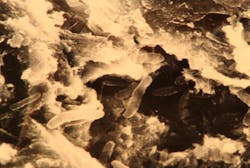

High-powered transmission electron microscopic assay has revealed calculus to be a porous mineralized structure—like a dry sponge—allowing viableMultiple studies in the literature show a relationship between subgingival calculus, inflammation, and microulcerations in the adjacent soft-tissue wall of the periodontal pocket. The bacteria within the calculus have the potential to release potent toxins into the tissues, inciting inflammation and causing the disease to progress. Periodontal pathogens, such as Porphyromonas gingivalis, are capable of reaching the bloodstream through the ulcerated pocket wall and have been found in the brains of patients with Alzheimer’s and in coronary atheromatous plaques.

- Cemental mounds. These sessile elevations on the surface of cementum are the former insertion sites of the collagen fibrils of the periodontal ligament. The underside of calculus has depressions that fit over the mounds, providing minimal retention (figure 3). Light root planing with a curette or ultrasonic scaler is sufficient for removal.

- Resorption lacunae. These defects may be pervasive and may be formed by persistent occlusal trauma or orthodontic treatment.8 Rapidly advancing periodontitis allows pathogenic microbiota to invade, colonize, and harden. The resultant calculus can be attached into the lacunae, making removal without surgery very difficult.

- Fractured calculus. Calculus can chemically bond to the hydroxyapatite crystalline structure of cementum, and that union can be stronger than the cohesive strength within calculus itself.9 When attempting to remove, the calculus can fracture and a basal layer remains firmly attached to the root. Repeated strokes with a scaling instrument result in a “burnished,” or smooth, surface that is often undetectable by a periodontal probe.